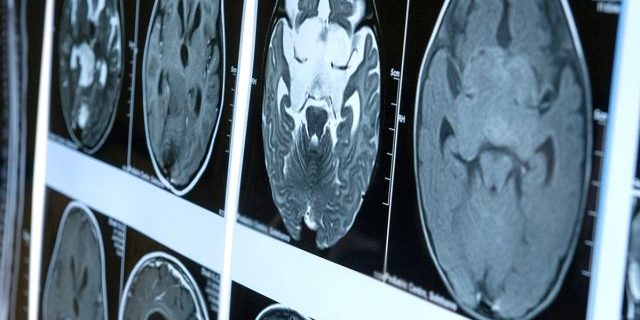

В мозге большинства пациентов, умерших от COVID-19, при вскрытии выявляются следы коронавируса, сообщает РИА Новости, ссылаясь на данные специалистов из Университетской клиники Гамбург-Эппендорф. Их исследование опубликовано в журнале The Lancet.

Специалисты обнаружили следы коронавируса в 53% случаев. Чаще всего их находили в клетках ствола мозга и отходящих от него нейронах. Кроме того, у 14% умерших также имелись очаговые ишемические поражения, а у 86% из-за разрушения близлежащих нейронов были аномально увеличены астроциты — поддерживающие клетки нервной ткани.

Однако авторы исследования назвали незначительными изменения в мозге из-за проникновения туда коронавируса.

Отмечается, что они не выявили его прямого разрушительного воздействия на центральную нервную систему.